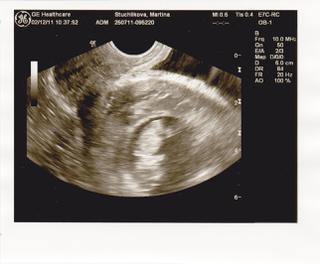

Moje info, miminko se má čile k světu, už má 3cm a vše je OK 🙂 přidávám fotečku, mimísek je hlavičkou dolů a má zkřížené hnátičky 😀 19.12 mě u Apolináře čeká screening, takže po cca 14 dnech zase to naše zlatíčko uvidíme 🙂 😀 krásně už kopalo nožičkama a máchalo ručičkama 😉